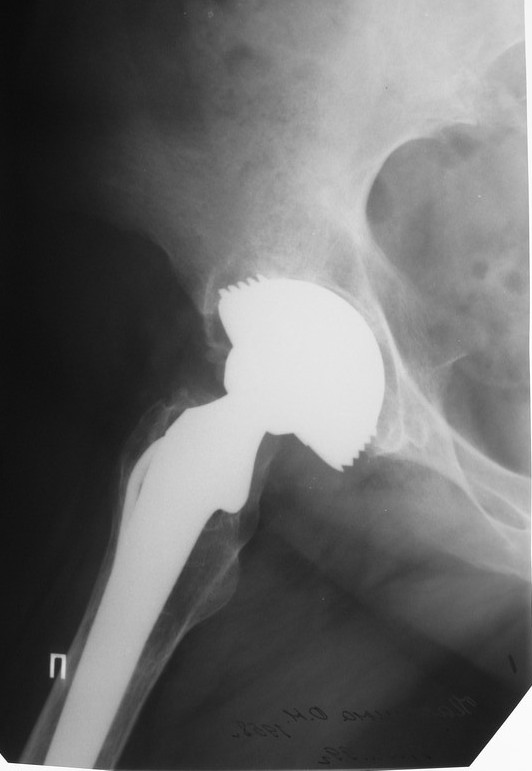

Уважаемые коллеги,в клинику поступила пациентка 51год с нестабильным антипротрузионным кольцом и вывихом эндопротеза.

В течени длительного времени у пациентки ревматойдный полиартрит с приемом преднизолона.В 1994году произведено эндопротезирование правого тазобедренного сустава бесцементным эндопротезом Biotronic.В 2000году по поводу нестабильности эндопротеза проведено ревизионное вмешательство-удаление чашки и ножки, некрэктомия.Установка антипротрузионного кольца, цементной чашки и ревизионной цементной ножки Beznoska.В 2007году выявлена клиникорентгенологическая картина нестабильности кольца.В 2008году пациентка упала, произошел вывих эндопротеза и дислокация кольца с переломом винтов.

Планируем ревизионное вмешательство-удаление кольца, чашки, винтов, пластика верхнего края вертлужной впадины массивным аллотрансплантатом с последующей установкойантипротрузионного кольца типа Burch-Shneider.